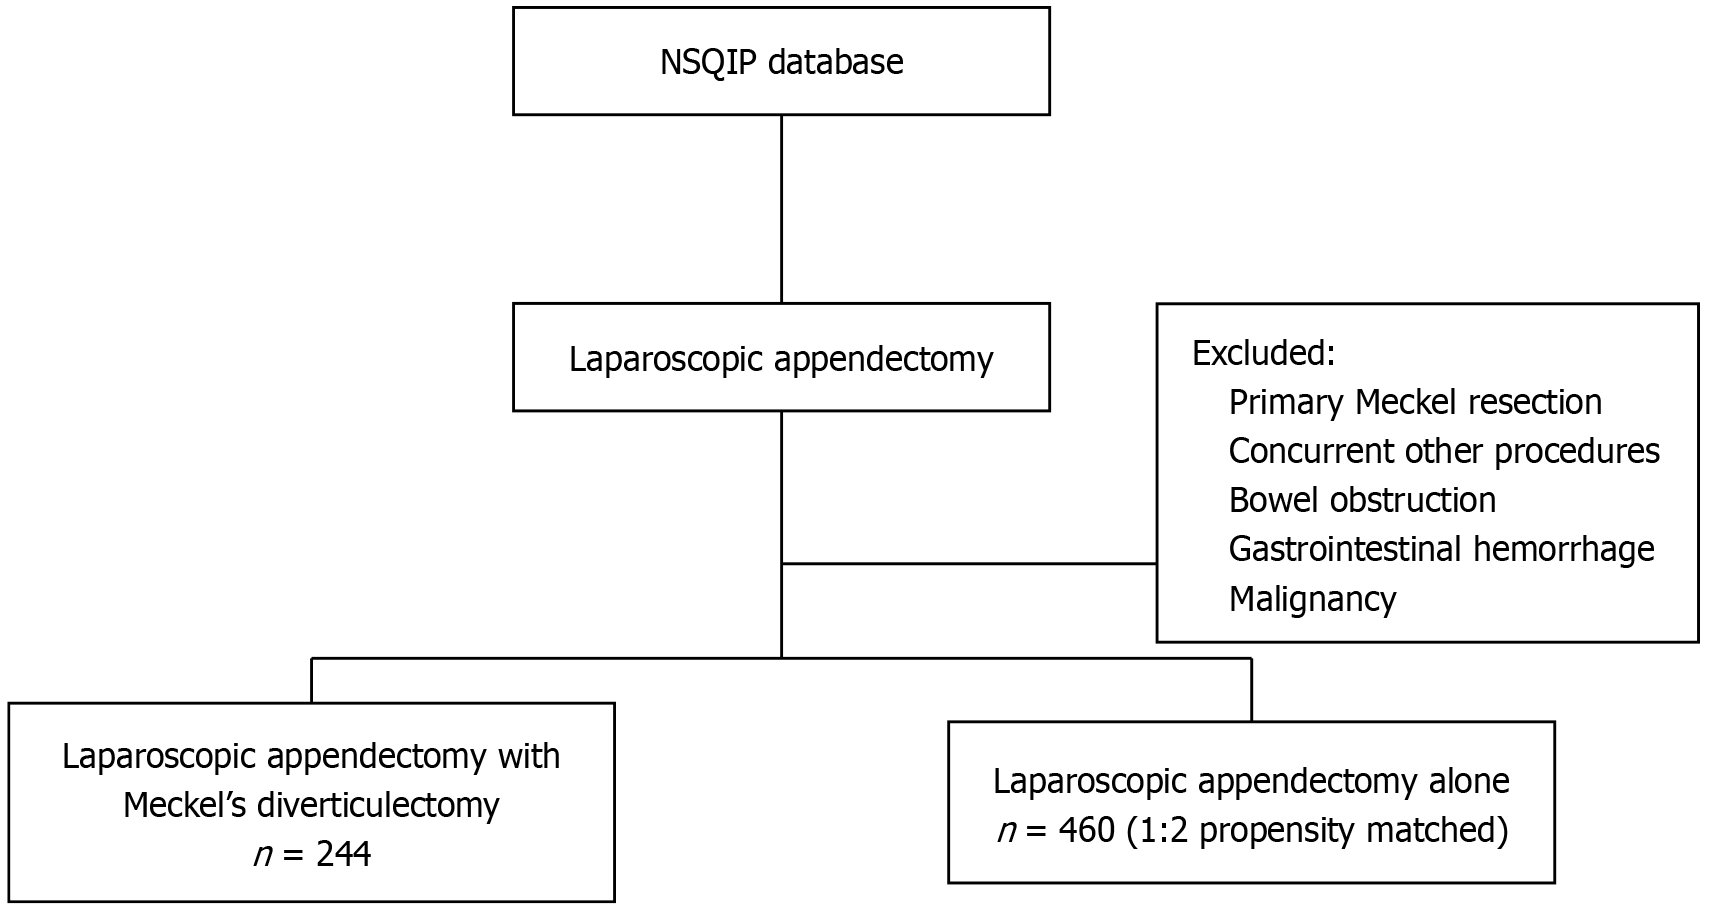

In addition to presenting our case report, we also performed a retrospective analysis of the ACS-NSQIP database during the 12 years preceding our patient’s procedure as these were the data available at the time of surgery. This database comprises over 140 patient variables from over 650 institutions nationally. Using the International Classification of Diseases, Ninth and Tenth Revision, Clinical Modification codes, we identified the following two adult patient cohorts: Patients undergoing concomitant Meckel diverticulectomy with appendectomy (MA) and those undergoing laparoscopic AA. All patients who underwent additional concurrent procedures, primary Meckel diverticulectomy, had bowel obstruction, had gastrointestinal hemorrhage, or had a cancer diagnosis were excluded (Figure 2). We performed propensity score matching for the patients in these two cohorts. Baseline demographics, comorbidities, and 30-day postoperative morbidity and mortality were compared. Furthermore, to compare between patient outcomes and 30-day postoperative morbidity and mortality, we performed univariate and 1:2 propensity-matched analyses. Lastly, operative time, the total length of hospital stay, 30-day postoperative infectious complications, 30-day non-infectious complications, and 30-day mortality were evaluated.